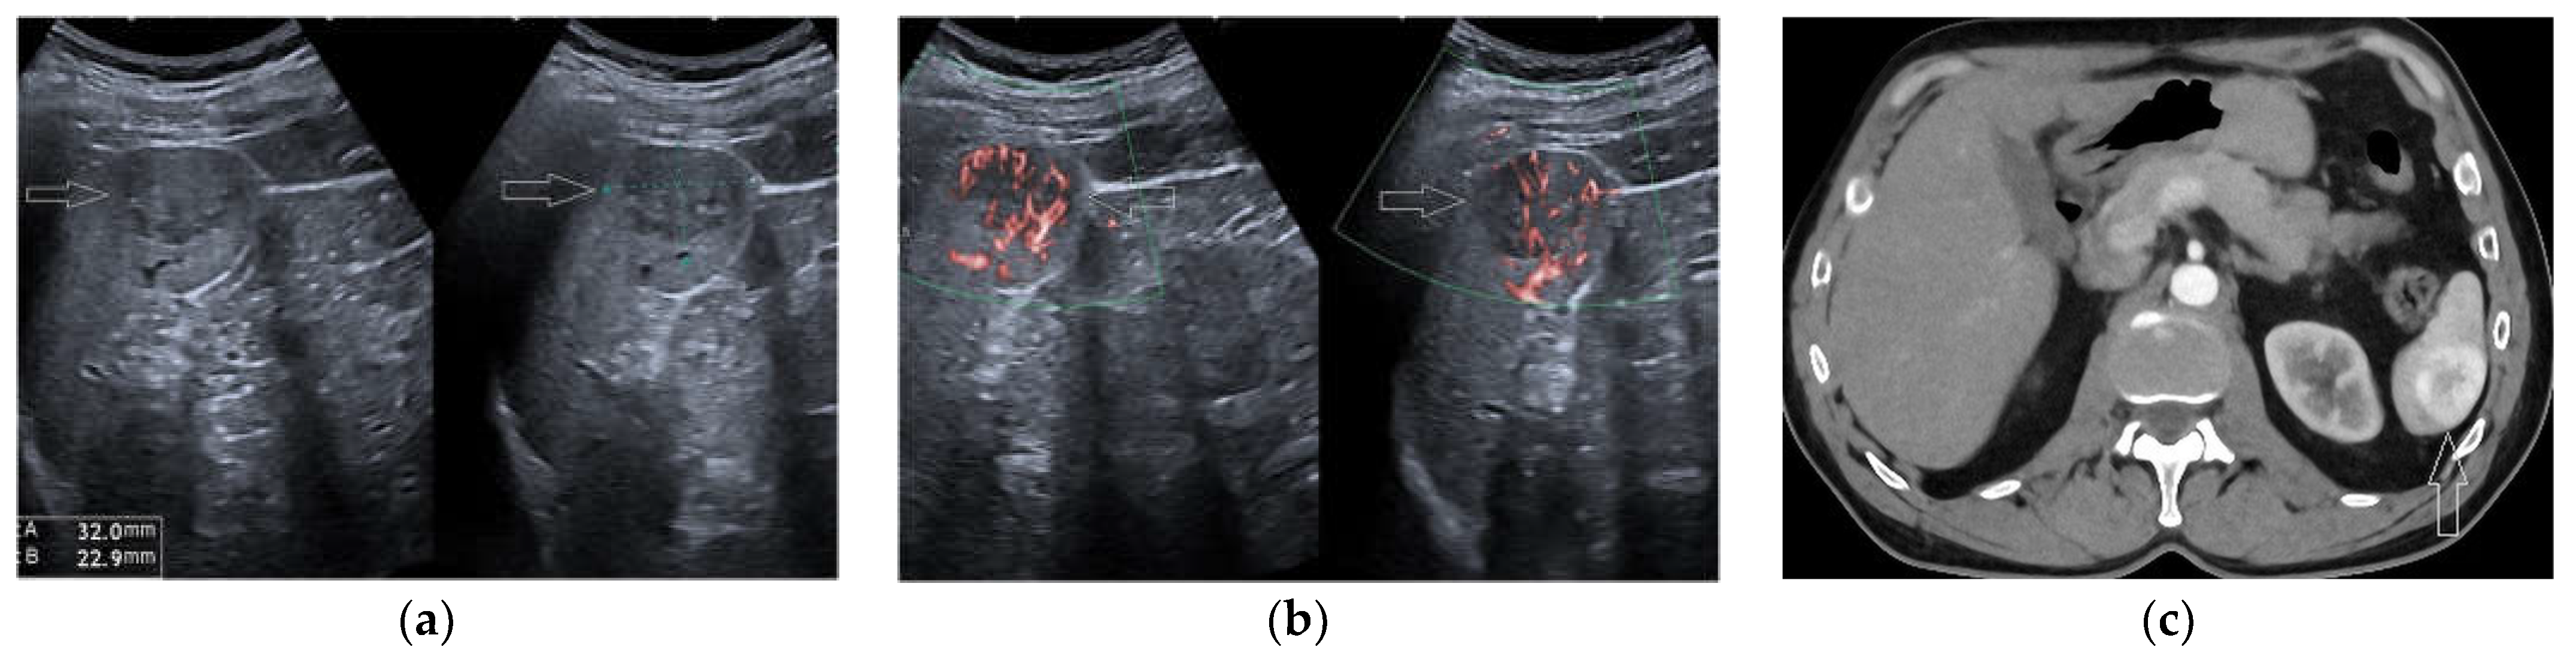

2.7. Solid Lesions

3. Risk of Malignancy and Pattern Recognition